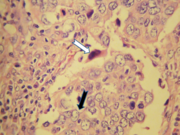

Carcinoma indiferenciado tipo células grandes (flecha negra). Célula ahusada eosinofílica (flecha blanca). H/E